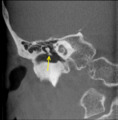

The malleus or hammer is a hammer-shaped small bone or ossicle of the middle ear which connects with the incus and is attached to the inner surface of the eardrum. The word is Latin for hammer or mallet. It transmits the sound vibrations from the eardrum to the incus.

The malleus is a bone situated in the middle ear. It is the first of the three ossicles, and attached to the tympanic membrane. The head of the malleus is the large protruding section, which attaches to the incus. The head connects to the neck of malleus, and the bone continues as the handle of malleus, which connects to the tympanic membrane. Between the neck and handle of the malleus, lateral and anterior processes emerge from the bone.[2]

The malleus is one of three ossicles in the middle ear which transmit sound from the tympanic membrane (ear drum) to the inner ear. The malleus receives vibrations from the tympanic membrane and transmits this to the incus.[2]